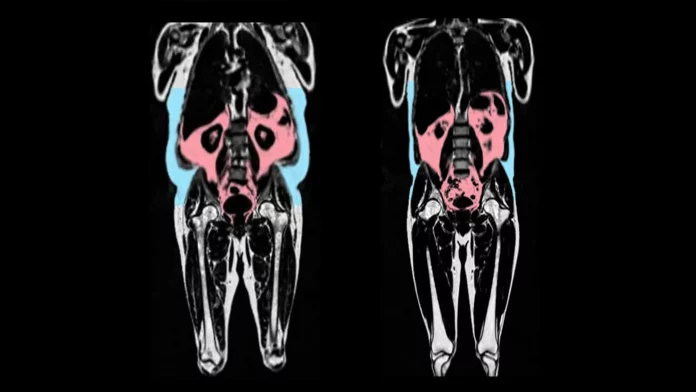

Within the research, printed within the European Coronary heart Journal, the scientists analyzed information from 21,241 individuals in UK Biobank, which incorporates complete physique imaging to map the quantity of fats and the place it’s situated within the physique.

The UK Biobank information additionally consists of detailed imaging of the center and blood vessels. Synthetic intelligence was used to analyse these photographs to seize indicators of organ getting older — similar to tissues turning into stiff and infected. A person was given a “coronary heart age” which may be in comparison with their precise age on the time of the scan.

The researchers discovered that quicker coronary heart getting older was linked to having extra visceral adipose tissue. Visceral adipose tissue is fats discovered deep contained in the stomach round organs such because the abdomen, intestines, and liver. Such a fats can’t be seen from the skin, and a few folks can have giant quantities of visceral fats regardless of having a wholesome weight.

Additionally they discovered variations between the sexes. Male-type fats distribution (fats across the stomach, typically known as ‘apple’ formed) was significantly predictive of early getting older in males.

In distinction, a genetic predisposition to female-type fats (fats on the hips and thighs, typically known as “pear” formed) was protecting towards coronary heart getting older in girls.

Professor Declan O’Regan, who led the analysis on the MRC Laboratory of Medical Sciences and Imperial Faculty London, and is the British Coronary heart Basis Professor of Cardiovascular AI, stated: “We have now recognized in regards to the apple and pear distinction in physique fats, but it surely hasn’t been clear howit results in poor well being outcomes. Our analysis reveals that “dangerous” fats, hidden deep across the organs, accelerates getting older of the center. However some forms of fats may shield towards aging- particularly fats across the hips and thighs in girls.”